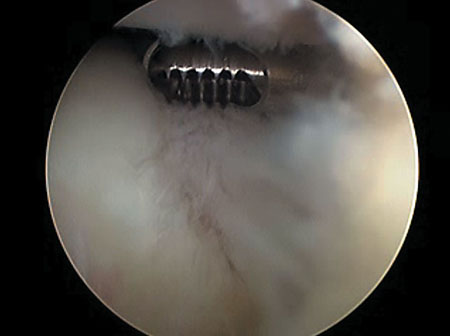

En cuanto a la técnica quirúrgica, todos los pacientes fueron sometidos a debridamiento articular artroscópico con Ringer Lactato. A todos se les realizó estabilización de las lesiones condrales con radiofrecuencia bipolar (RFB) (Arthrocare ®, coagulación en 1373 µm, 67°C y 40 W) (Fig.1) o condroplastía mecánica (CM) (Fig. 2) con motor artroscópico simple. Si presentaban lesiones meniscales inestables se les practicó una meniscectomía parcial según técnica habitual (Fig. 3).

Figura 1: Visión artroscópica intraarticular de rodilla. Observamos el tratamiento de cambios degenerativos condrales de cóndilo femoral con radiofrecuencia bipolar.